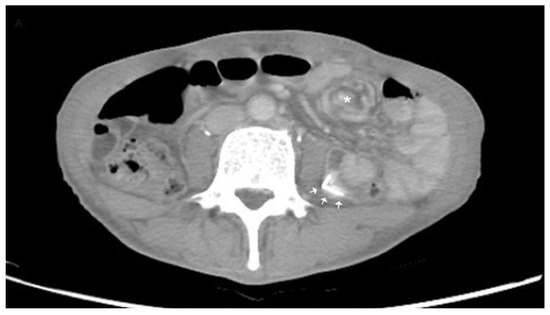

- Li, X.; Zhang, J.; Li, B.; Yi, D.; Zhang, C.; Sun, N.; Lv, W.; Jiao, A. Diagnosis, treatment and prognosis of small bowel volvulus in adults: A monocentric summary of a rare small intestinal obstruction. PLoS ONE 2017, 12, e0175866. [Google Scholar] [CrossRef]